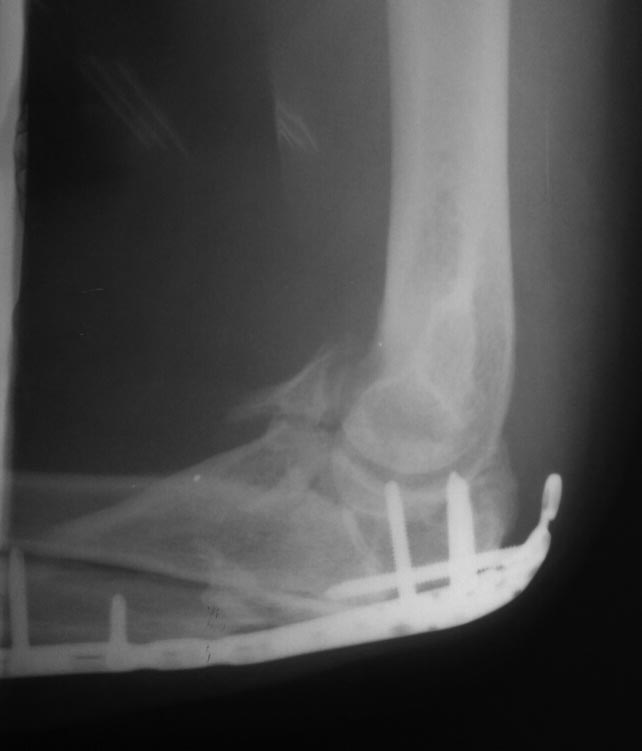

Консолидированный перелом проксимального отдела локтевой кости в условиях накостного остеосинтеза. Сросшийся перелом венечного отростка от февраля 2015.

Поступил к нам в учреждение спустя 4 месяца с момента оперативного лечения. Жалобы на ограничение движения в суставе, разгибание до 140-145., сгибание до 100-105. Сустав отечный, пальпация незначительно болезненная. При пассивных движениях определяется патологический хруст в суставе.Выполнено оперативное лечение - удаление металлоконструкции. Остеотомия локтевого отростка. При ревизии сустава - винт в суставе,в локтевой ямке отверстие от винта, имеется повреждение блока в виде дефекта хрящевой ткани полосами, перелом верхнего полюса головки лучевой кости(отломок 1\3 диаметра головки в полости сустава). В суставе выраженный спаечный процесс. Выполнено удаление рубцовой ткани, удаление отломка головки лучевой кости.

Отмечается консолидация венечного отростка,между отломков около 0.8 см рубцовые ткани. Выделение венечного отростка, рубцовые ткани удалены. Остеосинтез венечного отростка двумя винтами "типа Герберта".

Интраоперационно разгибание 180, сгибание 125-130.